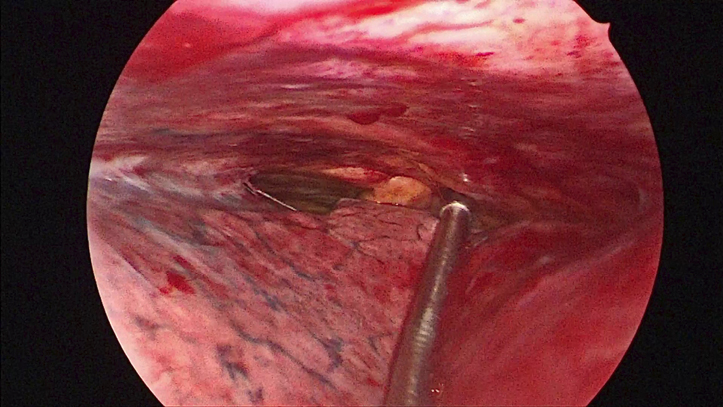

Abb. 1: Trotz Spontanatmung und Adhäsionen (links im Bild) reicht der Raum für das Pleuramanagement (Probeexzisionen, Pleurodesen) aus.